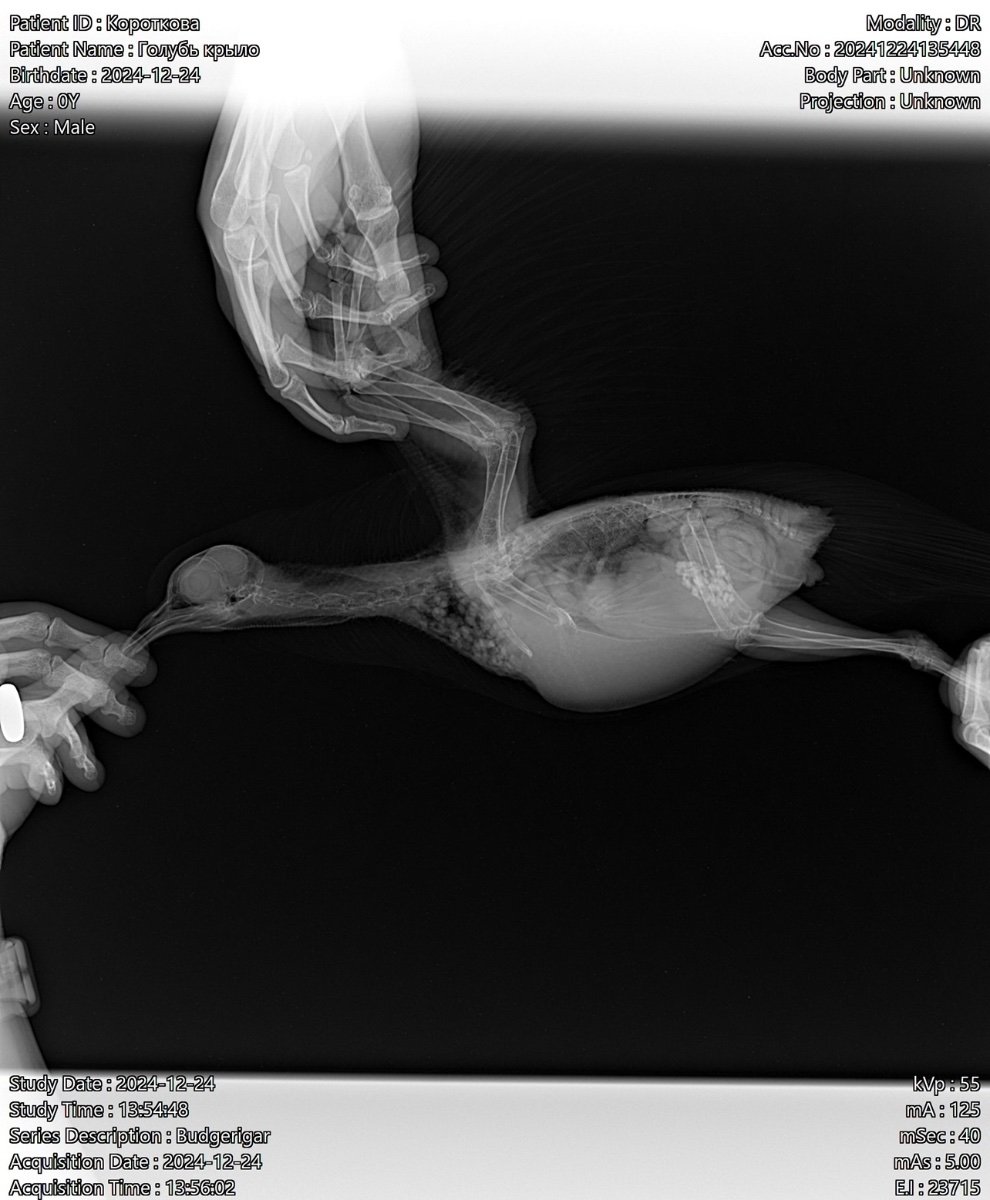

Татьяна Ладутько Опубликовано 4 января, 2025 #8 Опубликовано 4 января, 2025 @ekatereina здравствуйте. Антибиотики у вас назначены прям по самой верхней границы, даже чуть выше. Если брать вес 300гр. Ципролет - суточная 14мг выходит, а по верхней 12мг; Сумамед 25мг суточная, а по верхней 24мг, это если взять 80мг/кг@маленький принц посмотрите, пожалуйста, может немного снизить? @Ильяна в смысле "всё было хорошо"? У птицы пневмония и остеомиелит в луч.кости. Антибиотики назначены к месту. И прикрытие сильное. @Физкульт-привет! Странный вы, зачем экспериментируете на птицах с питанием, до вас это уже сделали врачи и учёные, поэтому есть составленные рационы питания, зависящие от конкретного периода жизни птицы и ее потребностей. А белок - один из самых важных составляющих питания.

Zosia Опубликовано 5 января, 2025 #18 Опубликовано 5 января, 2025 все, кроме ацинетобактер- мимо идет. Часть вообще из пробиотика (какой даете, кстати). Ципрофлоксацин- имеет очень большую "вилку" доз, от 5 до 20 мг/кг каждые 12 часов. Но указаны гриббы +++, так что нистатин вам обязателен, 60 000 ед на 100 гр веса в сутки,весь курс а\б плюс 4-6 дней. По рентгену. Остеомиелит под вопросом, хотя есть зона абсцесса Броди на лучевой кости. Птиц полетит, если все срастется. Так же- описание гнилостного запаха из глюва, что может говорить о трихомонозе. Так что плюсом- метронидазол в дозе 5 мг на 100 гр веса в сутки, не менее 12 дней. 1

ekatereina Опубликовано 5 января, 2025 Автор #21 Опубликовано 5 января, 2025 2 часа назад, ната1805 сказал: не считала дозировки на антибиотики-но бросилось в глаза витамин в12 в дозе 0, 3 мл-перебор.... суммамед пересчитала-вам назначено 25 мг в день-максимально допустимая-у меня с такой дозы-а я раз такую дозу давала-стал какать на 17 день лечение желтым-пришлось бросить... у вас еще и флук тяжелый-не забывайте-и ципрофлоксацин-прям дай бог сил вашему голубю это перенести... я не придираюсь-корм у вас какой то....так не должно быть-у вас почти одна красная чечевица.... так не кормят Это просыпанные зернышки, в миске у него перловка и зеленая гречка в основном. Но он ест мало. 9 часов назад, Zosia сказал: все, кроме ацинетобактер- мимо идет. Часть вообще из пробиотика (какой даете, кстати). Ципрофлоксацин- имеет очень большую "вилку" доз, от 5 до 20 мг/кг каждые 12 часов. Но указаны гриббы +++, так что нистатин вам обязателен, 60 000 ед на 100 гр веса в сутки,весь курс а\б плюс 4-6 дней. По рентгену. Остеомиелит под вопросом, хотя есть зона абсцесса Броди на лучевой кости. Птиц полетит, если все срастется. Так же- описание гнилостного запаха из глюва, что может говорить о трихомонозе. Так что плюсом- метронидазол в дозе 5 мг на 100 гр веса в сутки, не менее 12 дней. Спасибо! не поняла про мимо. Пробиотик никакой не даем, даже не подумала, что нужно. Какой лучше? Нистатин добавим, хорошо. Метронидазол добавлять прямо сейчас? К двум антибиотикам? Уточняю, потому что голубь мало ест с начала терапии, не станет ли ему еще хуже 1

Татьяна Ладутько Опубликовано 6 января, 2025 #22 Опубликовано 6 января, 2025 3 часа назад, Ильяна сказал: не понятна обоснованность всех этих препаратов. Сумамед от респираторки, выявлен микоплазмоз; Ципрофлоксацин от остеомиелита или абсцесса Броди; Дифлюкан- противогрибковое; Гептрал- гепатопротектор; Мелоксикам от боли. Зося ничего и не отменила, а ещё добавила метронидазол и нистатин. @ната1805 дозировки на а.б. идут даже немного выше верхней, я уже считала выше. ! И ещё раз предлагаю их снизить, т.к. курс длительный. @ekatereina если птичка плохо кушает - её обязательно нужно докармливать. У вас тяжёлое лечение, не дай бог птице похудеть! 2